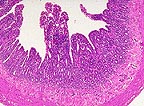

死亡動物からの組織の顕微鏡検査は、ウイルス性腸炎に一致しています。特に、繊毛先端に腸細胞の壊死があります。陰カは中等度から顕著に過形成性です。中等度から重度リンパ形質細胞の浸潤物と種々程度の繊毛萎縮、鈍化、融合、欠損がさらに長期の症例の腸に見られます。特徴的な腸の変化は感染後8ヶ月目に見られます。(原文ページの画像を参照ください)